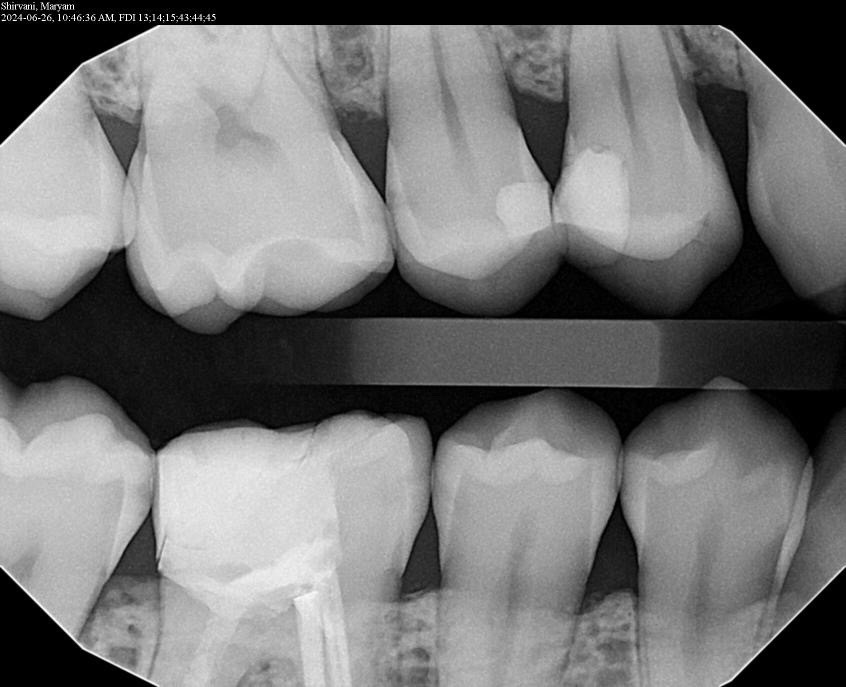

2. In the X ray bellow for which jaw periodontal bone loss is evident?